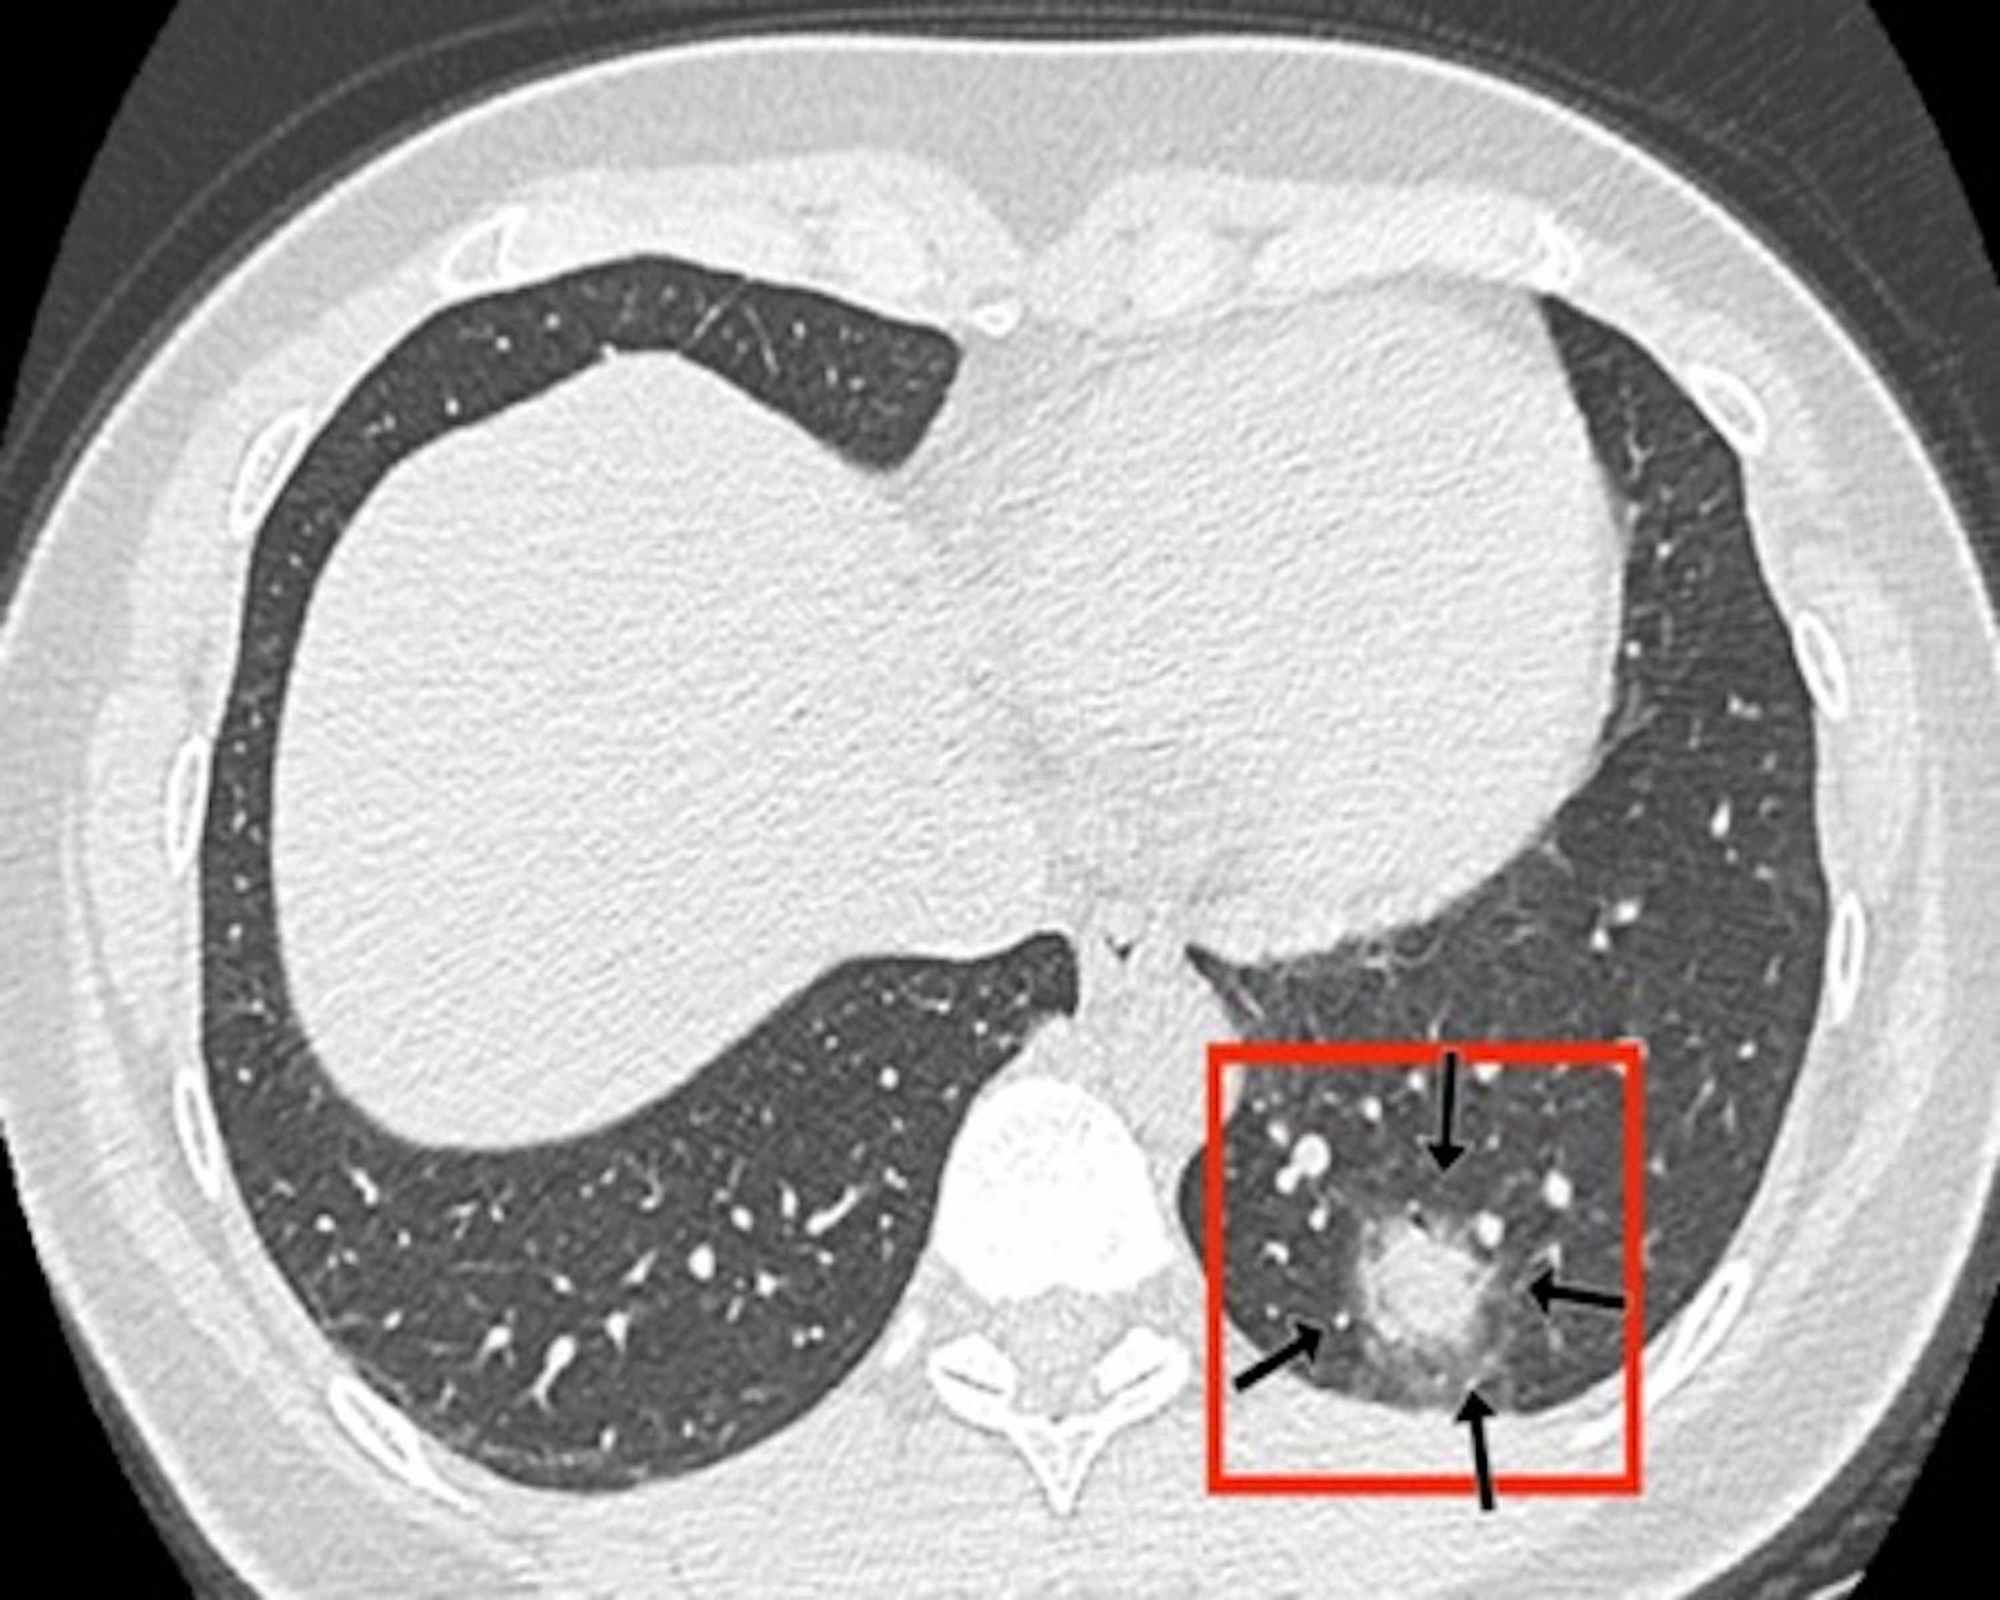

In the CT images, GGO plus consolidation was observed bilaterally in all 18 (100%) patients. No pure GGO or pure consolidation was encountered in our cohort. The predominant shape was amorphous (72%). Lesions showed no specific lobar predilection, but most lesions were localized posteriorly and peripherally.

The distinctive CT features in our cohort are summarized in Table 3, including GGO and consolidative patchy mostly amorphous (72%) lesions, bilateral posterior and peripheral multi-lobar lung involvement, pleural effusions, subpleural fibrotic lines, subpleural sparing, vascular engorgement, occasional crazy paving, occasional mediastinal lymphadenopathy, pleural thickening, lack of cavitation, and absence of reverse halo (atoll) signs.

Subpleural sparing, which was observed in this patient cohort, has never been reported before, whereas mediastinal lymphadenopathy has been reported occasionally in the literature in English [11]. Focal vascular engorgement, septal thickening, and a subpleural fibrotic line were seen frequently in our cohort, with frequencies of 83%, 72%, and 61%, respectively.

Patients’ CT features are presented in detail in Figures 3, 4, 5, 6, 7, 8. A majority of cases (56%) had moderate severity scores. There was no correlation between the severity score and mortality, p=0.790 (Table 4).